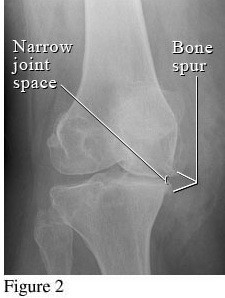

Hình ảnh của khớp gối trên phim X-quang: Khe khớp hẹp nhiều, gai xương có kích thước lớn, đặc xương dưới sụn, đầu xương biến dạng rõ.

Thoái hóa khớp gối giai đoạn 4 là giai đoạn nặng, sụn khớp bị bào mòn

Thoái hóa khớp gối đã bước vào giai đoạn nặng, sụn khớp bị bào mòn và bong tróc gần như hoàn toàn để lộ đầu xương rõ rệt. Khoảng không gian chung giữa hai đầu xương thu hẹp đáng kể, gai xương ngày càng lớn, chất nhờn bôi trơn khớp giảm nên gây ra hiện tượng ma sát giữa hai đầu xương, gây đau nhức xương khớp nghiêm trọng. Người bệnh xuất hiện một loạt các triệu chứng đau nhức liên tục, cứng khớp, khó vận động khớp, khó đi lại… ảnh hưởng đến sinh hoạt. Theo thời gian, thoái hóa khớp gối có thể gây biến dạng khớp hoàn toàn, gây lệch trục khớp…